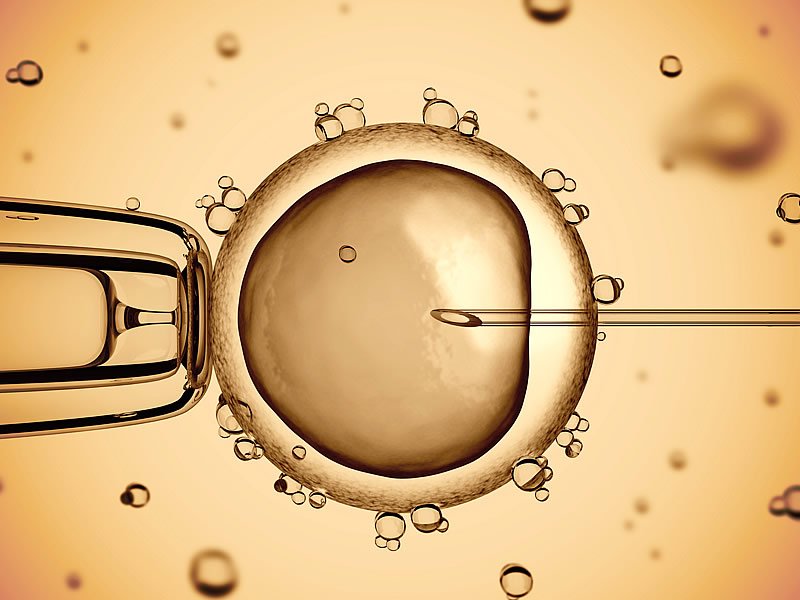

Aşılama için verilecek sperm örneğinin laboratuarda hazırlanmasında yüzdürme, yoğunlaştırma gibi yöntemler olup sperm değerlerine göre yöntem seçilebilir. Laboratuarda hazırlama işlemi yaklaşık iki saat sürmektedir. Hazırlama temelde basit bir işlem olmakla birlikte laboratuar ekibinin titiz ve özenli çalışması başarıyı etkileyecektir.

Çatlatma iğnesinden 24-38 saat sonra bir ya da ardışık günlerde iki kez, laboratuarda yıkanan ve hazırlanan spermlerle aşılama yapılabilir. Aşılama günü sabah erkekten 2-5 günlük perhiz sonrası alınan sperm örneği laboratuarda yıkanarak hazırlanır ve konsantre edilerek çok ince bir kateter ile rahime bırakılır. İşlem anestezi gerektirmez, çok basit ve kısadır, ağrısızdır. Normal bir jinekolojik muayene gibidir. Sperm rahime bırakıldıktan sonra 15 dakika istirahat sonrası hasta normal yaşantısına dönebilir. Cinsel ilişki kısıtlaması yapılmaz. Aşılama sonrası progesteron desteği olarak bazı ilaçlar verilebilir, ama şart değildir.